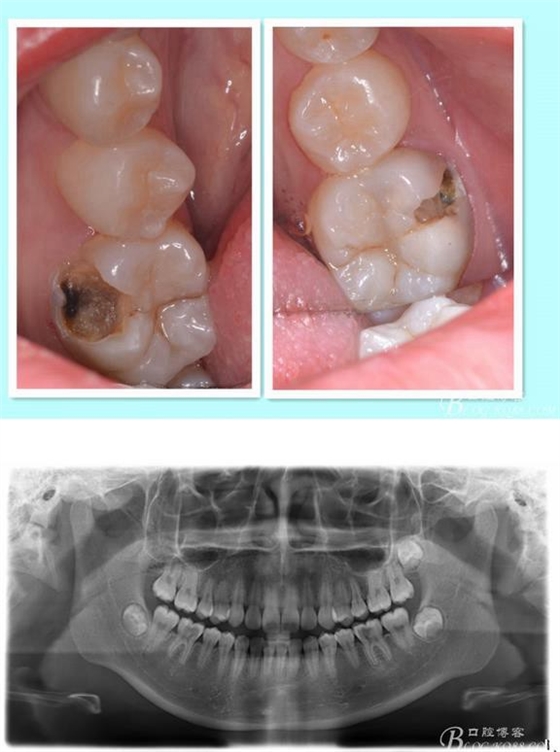

主訴:雙側(cè)下后牙疼痛一月余

病史:近一個月雙側(cè)下后牙疼痛,自發(fā)性 陣發(fā)性鈍痛,進食嵌塞加重,求診

查:雙側(cè)下6頰HE面齲壞 探診疼痛 冷熱刺激 遲反應(yīng)疼痛 叩診(-)頰側(cè)齲壞平齦

X線:雙側(cè)下6 齲壞已接近髓腔

診斷:雙側(cè)下6 慢性牙髓炎

治療方案:雙側(cè)RCT+CAD-CAM

這里我單做右側(cè)的詳細步驟